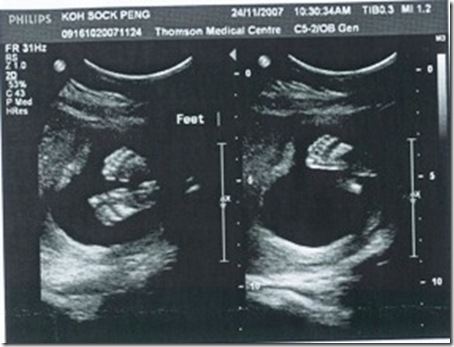

24/Nov/2007